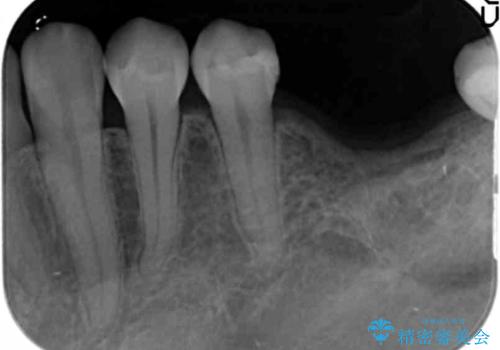

- 他院で抜歯後放置してしまった左下の奥歯の機能・見た目の回復を希望され来院されました。

放置したことによる影響か骨が吸収し、インプラント周囲に十分な骨が確保できないような状況であったため骨造成を併用したインプラント治療を計画します。